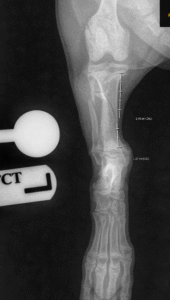

At just 4 months old, Lily (weighing only 3kg) jumped down awkwardly and suddenly became non-weight bearing lame on her left hind limb. She was seen by Emma, one of our orthopaedic surgeons, in our orthopaedic department. Radiographs of Lily’s leg revealed a long oblique fracture of the tibia and fibula, with instability felt on palpation.

Pre-op radiograph showing Lily’s fracture